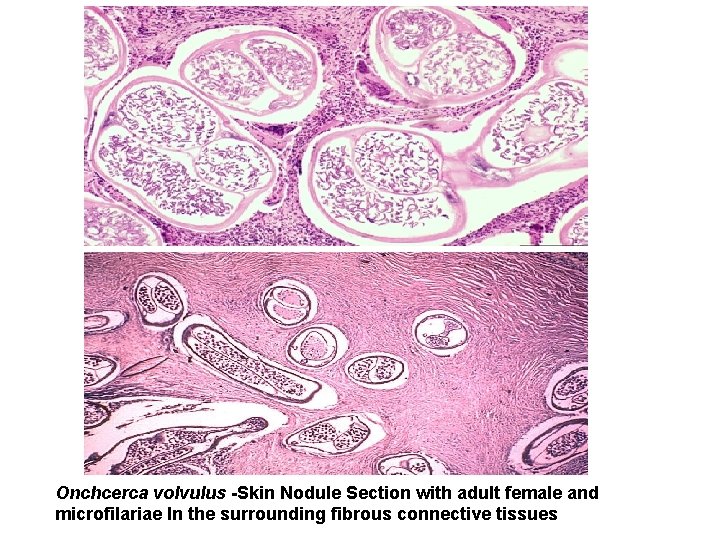

Onchcerca volvulus -Skin Nodule Section with adult female and microfilariae In the surrounding fibrous connective tissues